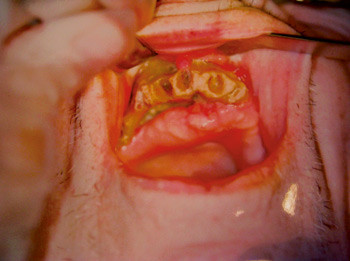

Osteonekrose i kjeven ved bruk av bisfosfonat ble først beskrevet i 2003 (1), nesten 30 år etter at medikamentgruppen ble tatt i bruk (2). Klinisk karakteriseres tilstanden av områder med blottlagt avaskulært bein i under- eller overkjeven. De aller fleste rapportene gjelder kreftpasienter behandlet med høye intravenøse doser av bisfosfonater som zoledronsyre (fig 1), men tilstanden forekommer også ved peroral bruk av andre bisfosfonatprepareter, bl.a. alendronsyre, mot osteoporose (fig 2).

Av de 20 bivirkningsmeldingene om bisfosfonatrelatert kjeveosteonekrose som kom til Statens legemiddelverk i 2006, gjelder to bruk av alendronsyre mot osteoporose. Den ene pasienten var en 78-årig kvinne som hadde brukt medikamentet i ni år, den andre en kvinne på 56 år som hadde brukt det i tre år (Harald Lislevand, Statens legemiddelverk, personlig meddelelse). Under arbeidet med denne artikkelen fikk vi kjennskap til ytterligere ett tilfelle av slik nekrose knyttet til bruk av alendronsyre mot osteoporose (fig 2).